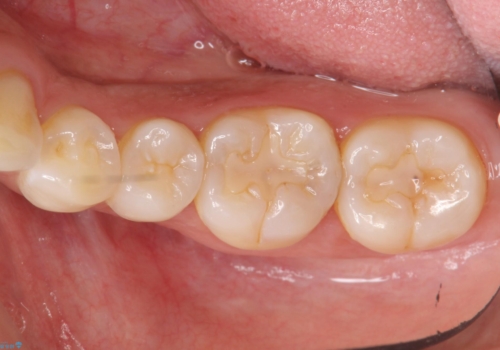

- 奥歯が虫歯になり、位置的に詰め物は難しかったため、被せものにする治療を行いました。

頬側に咬頭が一つ多い歯であったのと、歯肉に近い位置が虫歯になっていたため、被せものでしっかり覆う治療を行いました。